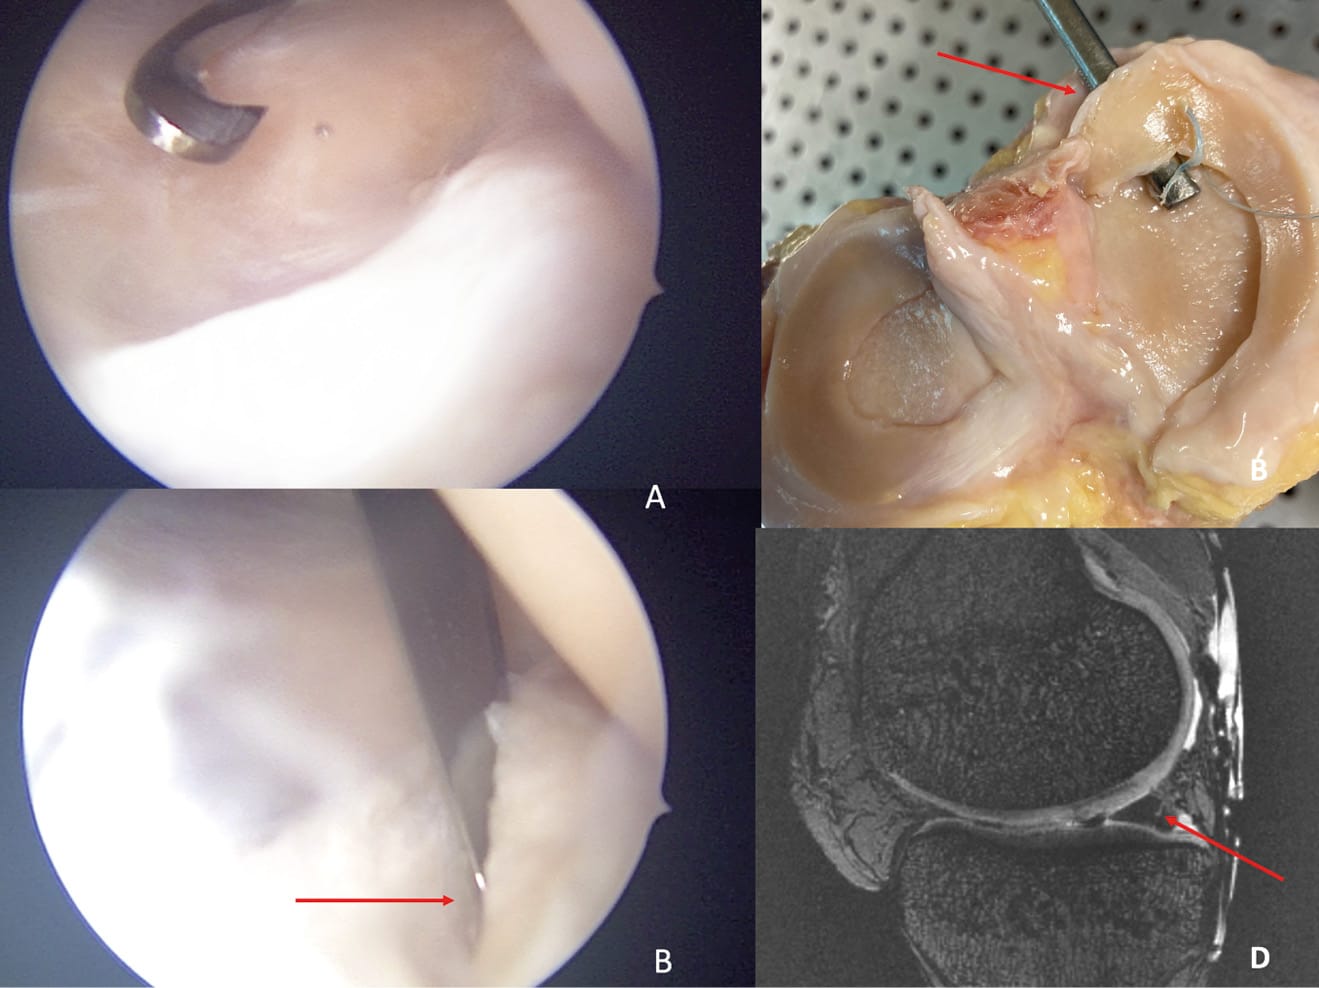

An initial series of 7T MRI imaging was performed on these native knees at progressive loads ranging from 0N to 1500N, equivalent to more than twice the body weight load. A second series of images was then taken on these same knees with the same loads after grade 4 medial meniscus ramp lesions [38] Thaunat M, Ingale P, Penet A, et al. Ramp Lesion Subtypes: Prevalence, Imaging, and Arthroscopic Findings in 2156 Anterior Cruciate Ligament Reconstructions. Am J Sports Med. 2021;49(7):1813-1821. doi:10.1177/03635465211006103 had been made under arthroscopy by a posteromedial instrumental approach (Figure 2).

Medial meniscus ramp lesions and lateral meniscus posterior root lesions are present in more than a third of primary and revision ACL reconstructions [24] Magosch A, Mouton C, Nührenbörger C, Seil R. Medial meniscus ramp and lateral meniscus posterior root lesions are present in more than a third of primary and revision ACL reconstructions. Knee Surg Sports Traumatol Arthrosc. 2021;29(9):3059-3067. doi:10.1007/s00167-020-06352-3. Medial meniscus ramp lesions (RL) are very common traumatic injuries with a prevalence of 21.9% (range, 9.0%-41.7%) at the time of anterior cruciate ligament (ACL) reconstruction [4], Brophy RH, Steinmetz RG, Smith MV, Matava MJ. Meniscal Ramp Lesions: Anatomy, Epidemiology, Diagnosis, and Treatment. J Am Acad Orthop Surg. 2022;30(6):255-262. doi:10.5435/JAAOS-D-21-00091[21] Kunze KN, Wright-Chisem J, Polce EM, DePhillipo NN, LaPrade RF, Chahla J. Risk Factors for Ramp Lesions of the Medial Meniscus: A Systematic Review and Meta-analysis. Am J Sports Med. 2021;49(13):3749-3757. doi:10.1177/0363546520986817. Ramp lesions are defined as a particular type of injury within the posterior horn of the medial meniscus and its menisco-capsular attachments. [38] Thaunat M, Ingale P, Penet A, et al. Ramp Lesion Subtypes: Prevalence, Imaging, and Arthroscopic Findings in 2156 Anterior Cruciate Ligament Reconstructions. Am J Sports Med. 2021;49(7):1813-1821. doi:10.1177/03635465211006103 Among the different types of ramp lesions, meniscocapsular junction tears (type 1) were the most common, followed by type 4 (complete tear in the red zone) [38] Thaunat M, Ingale P, Penet A, et al. Ramp Lesion Subtypes: Prevalence, Imaging, and Arthroscopic Findings in 2156 Anterior Cruciate Ligament Reconstructions. Am J Sports Med. 2021;49(7):1813-1821. doi:10.1177/03635465211006103.